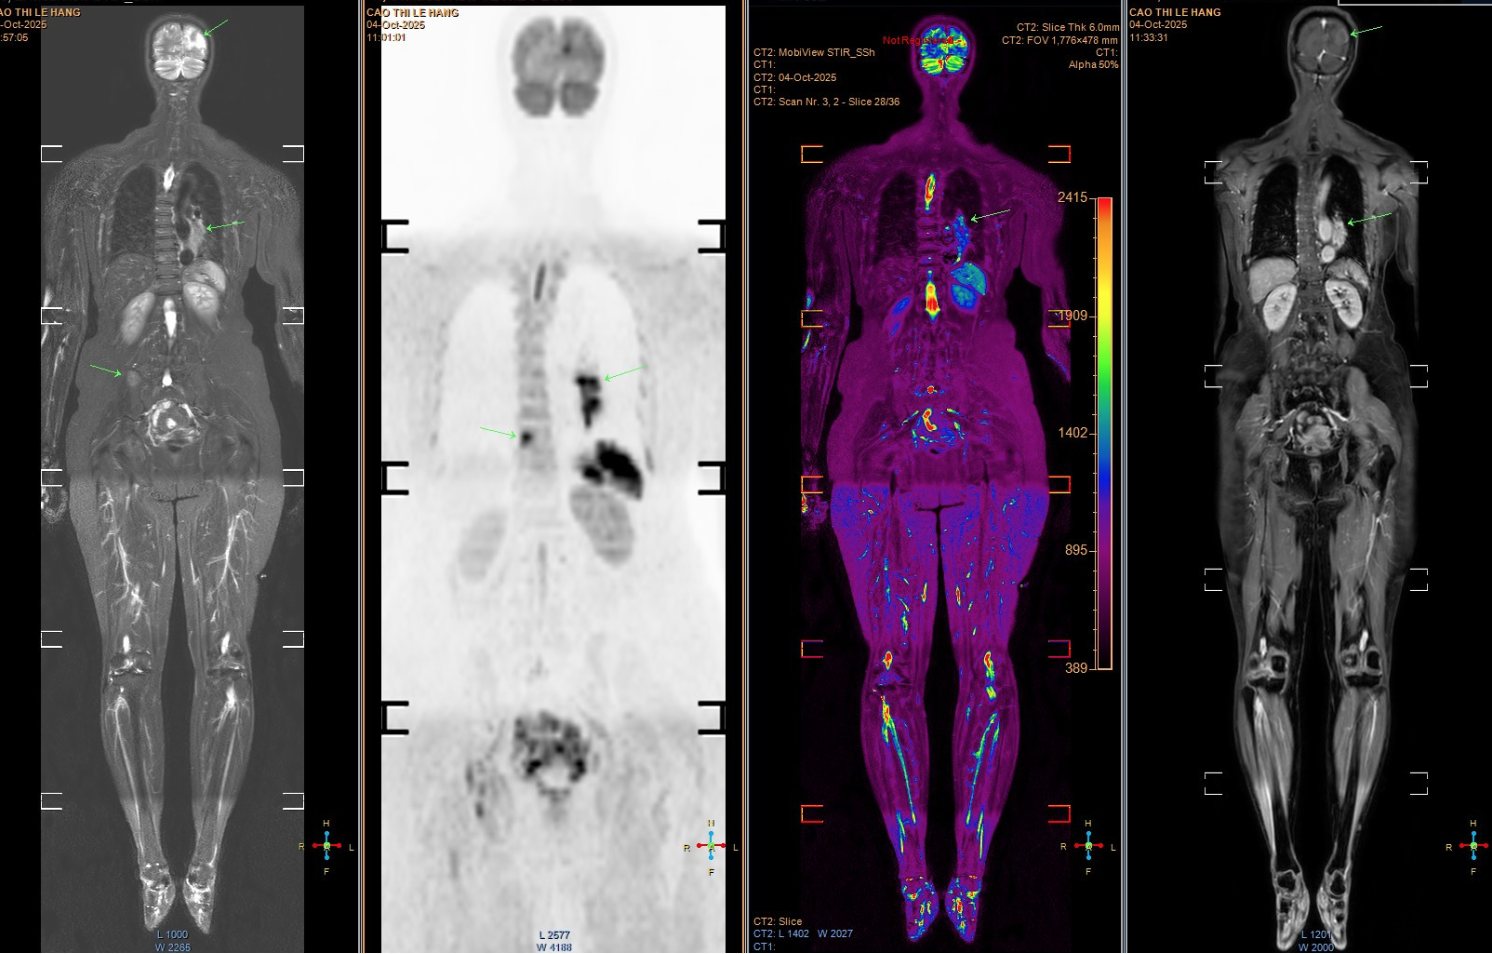

Tuy nhiên, các triệu chứng ngày càng nhiều và nặng hơn, bệnh nhân mới chịu đi khám sức khỏe. Kết quả chụp MRI cho thấy nhiều ổ tổn thương di căn dạng biểu mô tuyến. Khi chụp CT ngực, bác sĩ phát hiện một khối u lớn ở đáy phổi trái, xác định là ung thư phổi giai đoạn muộn, đã di căn sang nhiều cơ quan, trong đó có não bộ. Tiên lượng bệnh rất xấu.

Hình ảnh chụp tổn thương di căn của bệnh nhân. (Ảnh: Bác sĩ cung cấp)